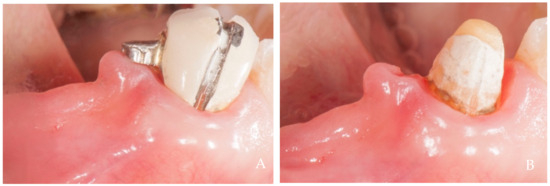

2. Clinical Examples of Oral Soft Tissue Growth